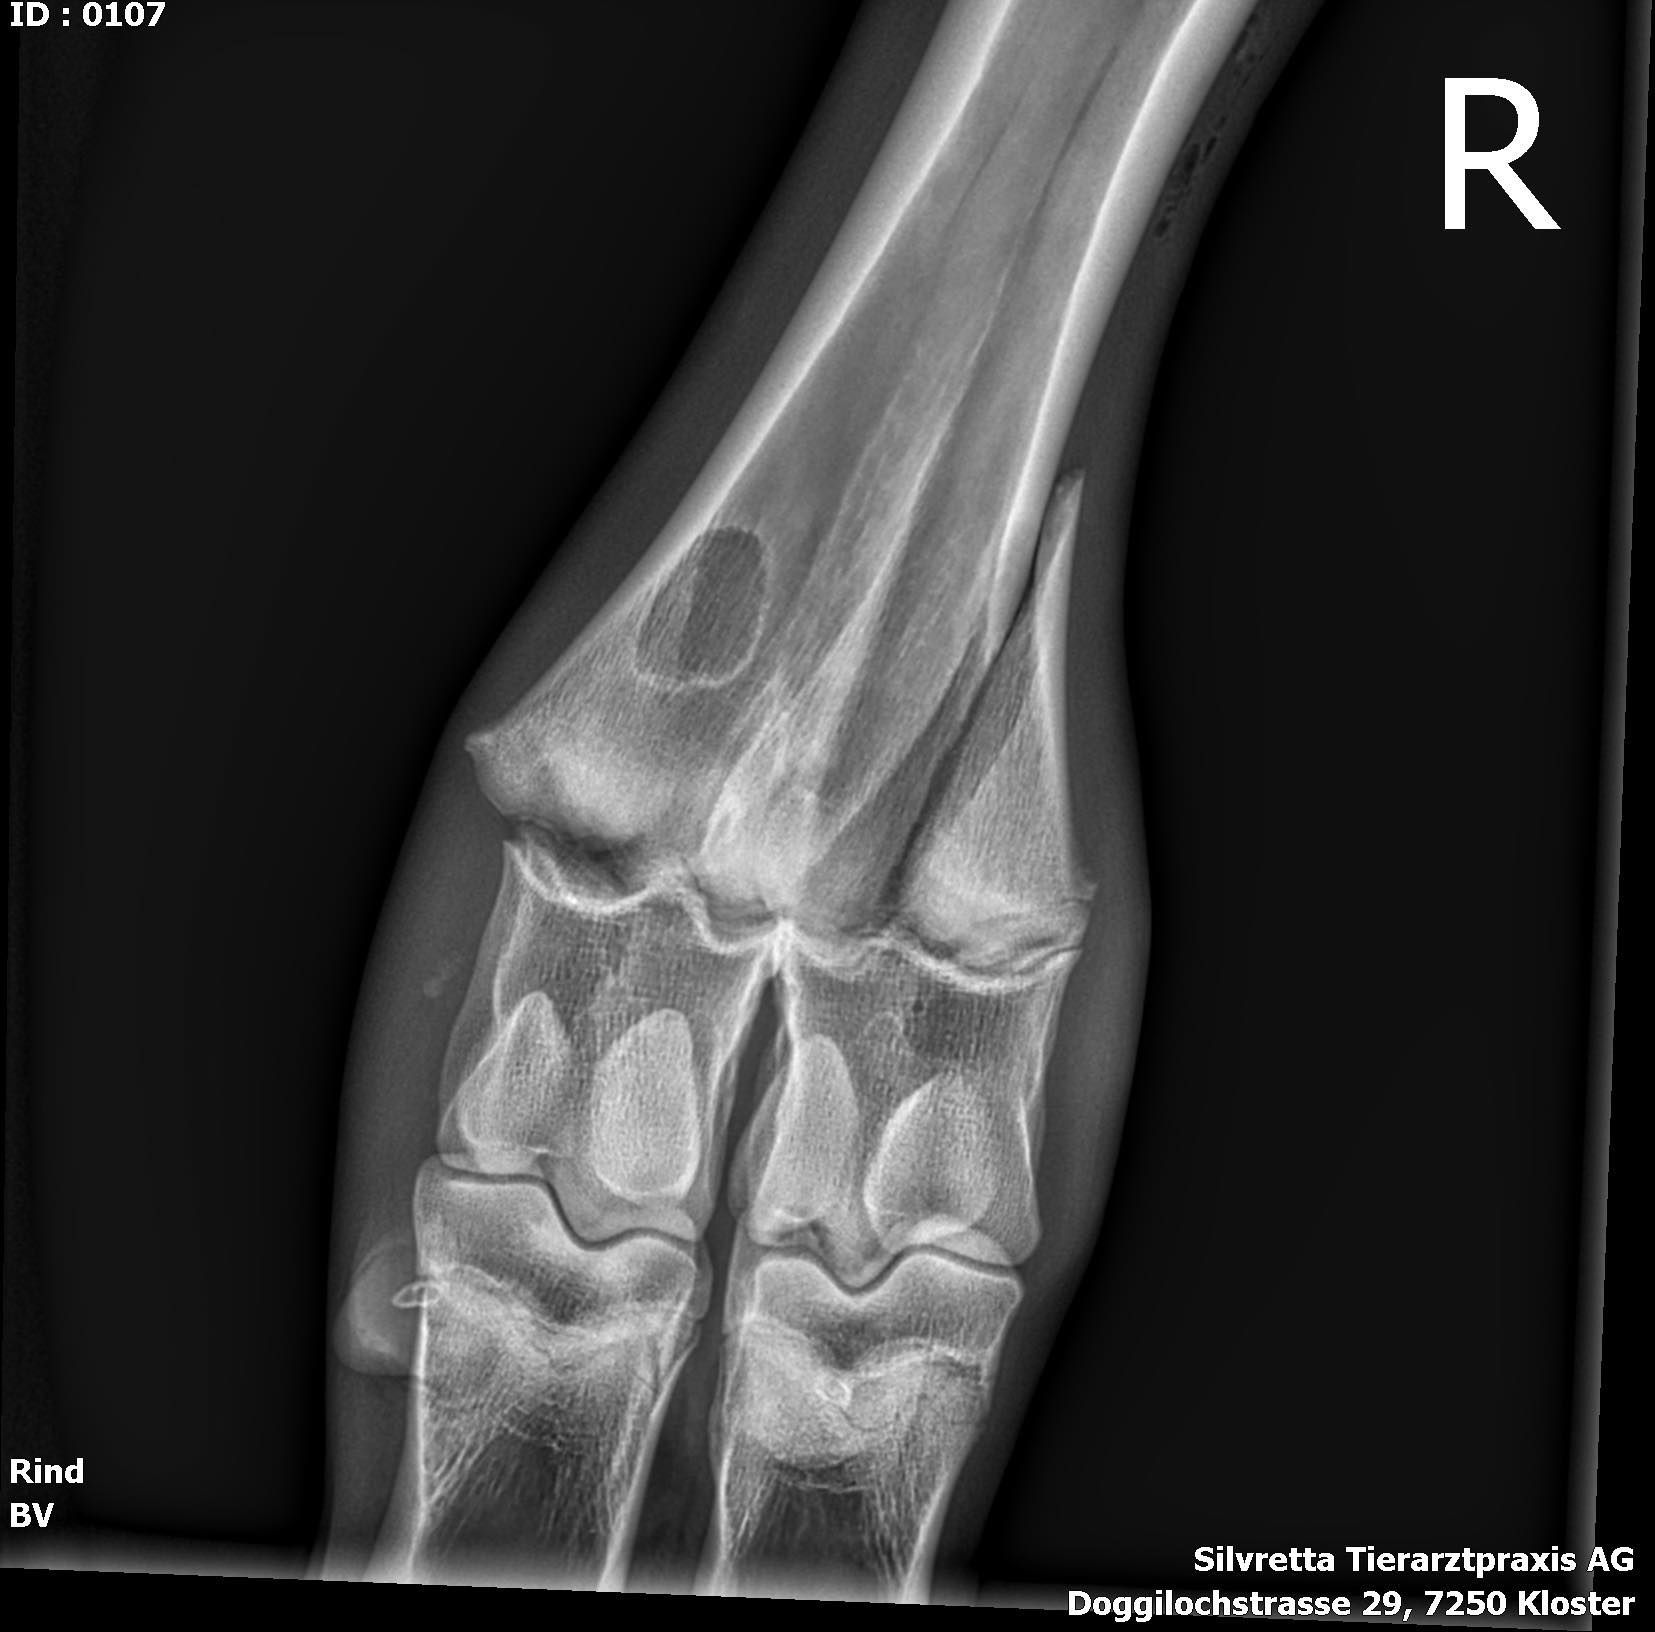

In diesem Monat stellen wir zwei Vierbeiner aus der Nutztierabteilung vor. Es sind Sissi und Vinja. Beide waren auf der Alp, beide haben den Anschluss zur Herde verloren und bei beiden sind die Besitzer zum Entschluss gelangt, sie frühzeitig nach Hause zu nehmen. Gut so, denn obwohl die Rindlein noch ein gutes Stück alleine auf der Alp gelaufen sind, stellte sich bei unserer Untersuchung heraus, dass beide eine Fraktur am Bein aufweisen. Kannst du sie erkennen?

Sissi in der Nähe des Fesselgelenkes (Röntgenbild 1 ) - Vinja am Ellbogen (Röntgenbild 2)

Sie sind beide noch jung und voll im Wachstum. Bei den Knochen geschieht die Streckung des Knochens von der sogenannten Wachstumsfuge aus. Die Fraktur von Sissi verläuft quer durch eine solche Fuge und gleichzeitig ist der lange Röhrenknochen längs bis in die Fuge gebrochen. Obwohl die Knochenteile sichtbar verschoben waren, ist Sissi noch tapfer gelaufen. Der Fachausdruck für diese Art von Fraktur heisst übrigens „Salter-Harris‘ Typ 2.